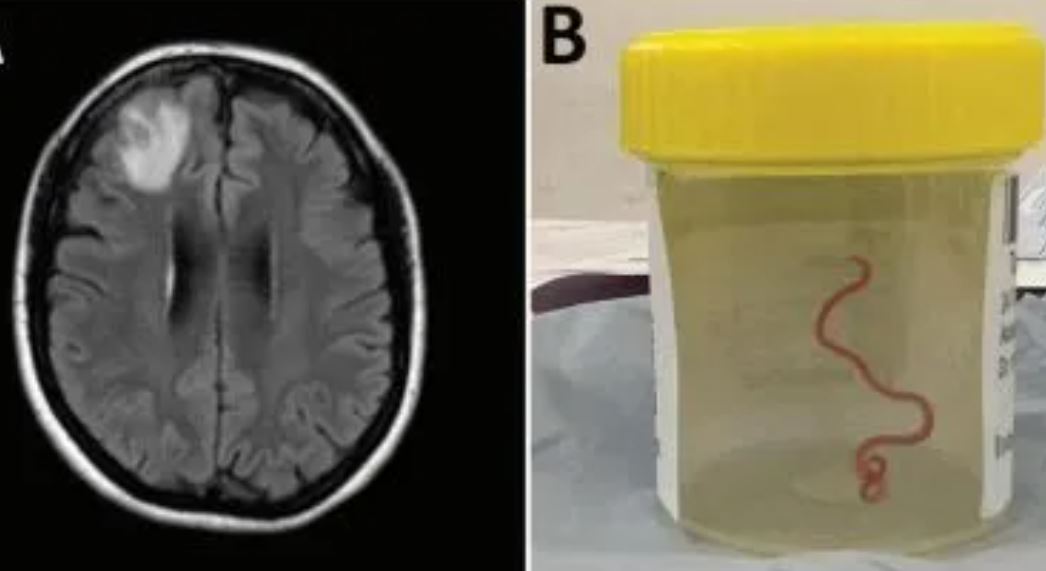

O verme, da espécie Ophidascaris robertsi, foi retirado vivo e já estava no terceiro estágio de vida. Ele foi descoberto após a mulher apresentar perda de memória, febre, tosse e uma lesão grave no lobo frontal direito do cérebro, onde estava o verme.

A princípio, ela foi diagnosticada com pneumonia, mas com a evolução dos sintomas para lapsos de memória desconexa e depressão, os médicos realizaram uma biópsia da lesão e acharam o verme.